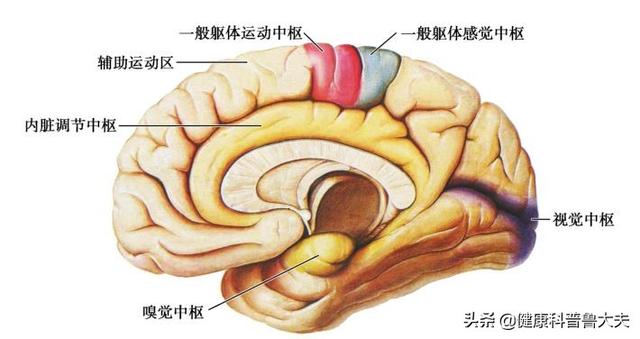

Notre cerveau gère presque toutes les fonctions de notre corps et est connu comme le commandant du corps. Le cerveau dépend du sang pour transporter l'oxygène et les nutriments dont il a besoin. Lorsque les vaisseaux sanguins sont bloqués pour diverses raisons, le cerveau est incapable d'obtenir de l'oxygène et des nutriments et meurt, entraînant la perte de fonctions de notre corps, ce qui est appelé infarctus cérébral. Les fonctions des différentes parties du cerveau étant différentes, les patients auront des séquelles plus ou moins importantes selon la localisation et l'étendue de la nécrose. Certaines personnes peuvent n'avoir qu'un léger vertige et découvrir qu'elles ont subi un infarctus cérébral lorsqu'elles se rendent à l'hôpital pour un examen (la plupart des patients atteints d'infarctus cérébral lacunaire sont découverts au cours de l'examen). Certains patients garderont des séquelles telles que l'hémiplégie, l'immobilité, la cécité, le retard mental, voire la mort.

Symptômes associés à un infarctus cérébral léger

Notre cerveau et les vaisseaux sanguins cérébraux sont un système très complexe, il y a de grandes artères, de petites artères, des artères pénétrantes, des artères basilaires, certains vaisseaux sanguins appartiennent aux vaisseaux de la circulation antérieure, d'autres aux vaisseaux de la circulation postérieure, selon les différentes parties du vaisseau sanguin infarci, la formation du cerveau de l'impact sur la santé est également différente, et les symptômes associés sont également différents, généralement dit, si le problème de l'infarctus cérébral n'est pas trop grave, en raison du site d'obstruction, de l'obstruction D'une manière générale, s'il s'agit d'un problème moins grave d'infarctus cérébral, en raison des différents sites de blocage, des degrés de blocage et des parties du cerveau touchées, les personnes atteintes d'infarctus cérébral peuvent présenter les symptômes suivants -

- Si la partie du blocage vasculaire cérébral affecte la partie du cerveau qui dirige les mouvements du corps, des symptômes tels que l'hémiplégie, l'ataxie, l'incapacité à marcher en ligne droite et la susceptibilité aux chutes peuvent apparaître.

- Si les vaisseaux sanguins cérébraux sont embolisés, ce qui affecte l'irrigation sanguine du cerveau, certains patients peuvent également souffrir de vertiges, de maux de tête, voire de nausées et de vomissements, et d'autres peuvent présenter des symptômes tels que des pertes de connaissance passagères.

- Si le blocage vasculaire cérébral affecte les zones fonctionnelles du cerveau dans le domaine de la déglutition et de la vocalisation, les personnes souffrant d'un infarctus cérébral léger ont tendance à souffrir d'aphasie, de dysphonie, de dysphagie, de paralysie faciale, et lorsque cela se produit, cela s'accompagne souvent de troubles légers des mouvements de la main, tels qu'une légère faiblesse de la main et des troubles de la motricité fine.

- Si l'obstruction des vaisseaux sanguins cérébraux affecte la zone du cerveau responsable de la sensation, des symptômes en termes de déficience sensorielle ou d'anomalie sensorielle, tels que l'engourdissement des membres asymétriques dans la moitié du corps et la perte de la sensation de douleur et de température, peuvent survenir.

- Si l'obstruction des vaisseaux sanguins cérébraux affecte le nerf central de la vision, elle peut provoquer des anomalies visuelles, notamment une vision anormale, des hallucinations visuelles, voire une incapacité à voir et des troubles des mouvements oculaires.

Examinons tout d'abord le terme "infarctus cérébral léger". En général, si l'on classe le degré de la maladie, on trouve les expressions "léger", "modéré" ou "grave", et avec l'infarctus cérébral, cela signifie que le degré de l'infarctus cérébral est relativement faible. L'infarctus cérébral est le nom abrégé de la maladie "infarctus cérébral" ou "infarctus cérébral", l'infarctus cérébral et l'infarctus cérébral sont des noms différents de la même maladie, seuls les grands et les petits noms sont différents. L'infarctus cérébral est l'infarctus des cellules cérébrales, la signification de la mort des cellules cérébrales, les cellules cérébrales sont l'unité de base du tissu cérébral, le tissu cérébral est divisé en cerveau, mésencéphale, cervelet, tronc cérébral.

Chaque tissu cérébral et chaque zone fonctionnelle sont différents, tout comme le rôle qu'ils jouent.

Par exemple, l'hémisphère gauche du cerveau régit les mouvements du côté droit du corps et l'hémisphère droit contrôle les mouvements du côté gauche du corps ; le lobe préfrontal du cerveau est responsable de la pensée, de la planification et est associé aux besoins et aux émotions de l'individu. Le lobe pariétal du cerveau - répond aux sensations de douleur, de toucher, de goût, de température, de pression ; cette zone est également associée aux mathématiques et à la logique. Lobe temporal du cerveau - Responsable du traitement des informations auditives, il est également associé à la mémoire et aux émotions. Lobe occipital du cerveau - Responsable du traitement des informations visuelles. Le système limbique du cerveau est impliqué dans la mémoire et dans les aspects comportementaux et émotionnels. Il est impliqué dans tous les aspects du corps humain tels que les sensations, les mouvements, les émotions et la mémoire.

Par exemple, la fonction du cervelet est étroitement liée à la fonction d'équilibre du corps. La fonction du tronc cérébral est principalement de maintenir la vie de l'individu, y compris le rythme cardiaque, la respiration, la digestion et d'autres fonctions physiologiques importantes.

Chaque partie du tissu cérébral a donc une fonction différente des cellules cérébrales. Si des cellules cérébrales meurent dans cette partie, la fonction de cette partie est diminuée ou perdue. Par diminution, on entend que la zone de mort cellulaire est plus petite, et par perte, on entend que la zone de mort cellulaire est plus grande.